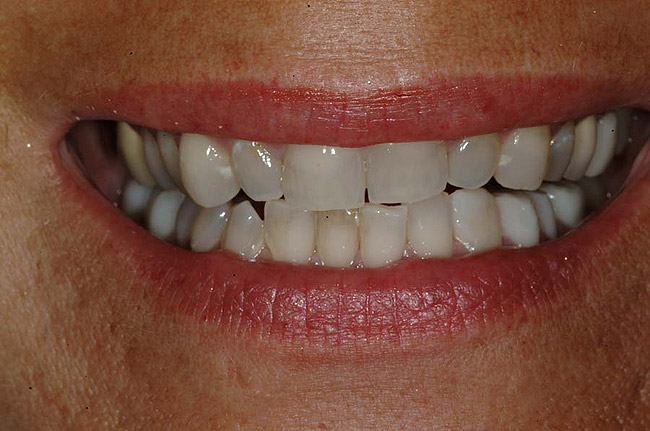

For example, before initiating the cementation process, preparations must be thoroughly cleansed (Figure 3), and adequate hemostasis and isolation should be ensured (Figure 4). Although newer generations of adhesives have been shown to be more tolerant of saliva contamination,7 proper isolation and hemostasis are still advisable because saliva and blood contamination cannegatively influence the bond strength of some bonding systems.8,9 Also,consider that resin cements are preferred for esthetic restorations, including porcelain laminate veneers.10,11 Successful use of these cements is dependent upon the incorporation of proper ceramic conditioning and tooth-surface treatment (ie, multiple-step total etch or self-etch adhesive)(Figure 8');" rem="#ip:figure5 through Figure 8">Figure 5 through Figure 8) to avoid incompatibility issues with the chosen cement and/or enhance the mechanical interlocking that occurs between the porcelain/resin-cement/tooth interfaces.10-13

<span id=Figure 4" border="0" height="199" hspace="0" src="/media/6771" title="Figure 4" width="300" />

Figure 4 To ensure adequate cervical access and promote hemostasis, a viscous, gingival retraction paste containing aluminum chloride (Expasyl™, Kerr Corporation) was placed in the sulci surrounding the preparations.